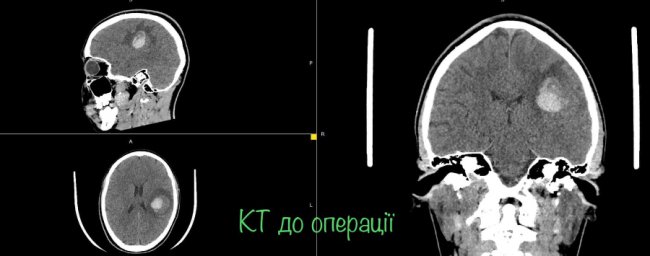

На МРТ виявили пухлину головного мозку з крововиливом в лівій домінуючій (важливішій) півкулі, в якій, власне, окрім центрів, які рухають кінцівками однієї половини тіла, розташований дуже важливий центр мови.

"Саме тому єдиний варіант врятувати здатність розмовляти можна тільки провівши таке втручання у свідомості. Тобто під час операції на головному мозку потрібно розбудити пацієнта. Потрібно не просто розбудити, а ще й знайти центр мови, який у кожного з нас розташований по-своєму, а тоді видалити пухлину за короткий час пробудження (близько години). І після цього знову ввести в наркоз", - розповідає Ловга.